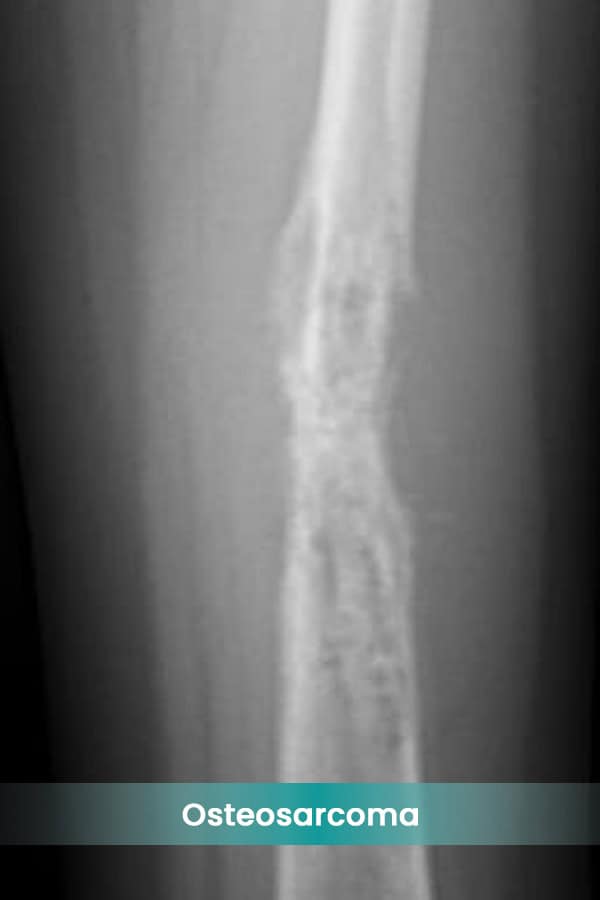

- Osteosarcoma